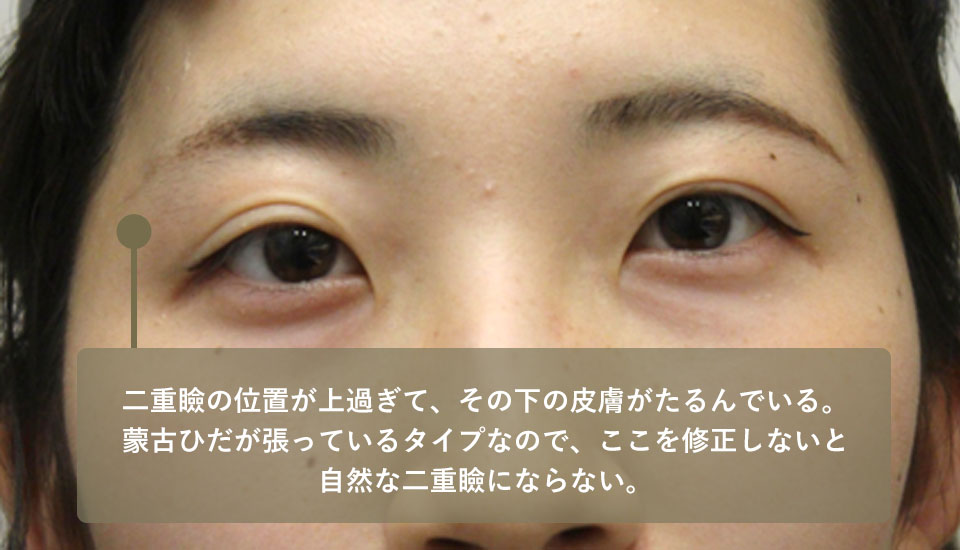

Since the shape of the eyelid became strange after the surgery, she underwent another revision surgery (skin excision) at the Plastic Surgery Department of Hospital C. However, the shape of the eyelid was still strange, so she came to our hospital hoping for a revision.

I would guess that the heavy eyelids were created exactly as they were in the previous surgery, but the heavy eyelids were created too high. We often see patients in a similar condition after cosmetic or plastic surgery for droopy eyelids.

The position of the eyelid is not necessarily higher than the eyelid should be. If the eyelids are not in the proper position, the skin under the eyelids will sag, resulting in this condition.

The size of the black eye has increased, but the skin laxity has increased relative to the size of the eye, and the position of the eyelid is unnatural. Our surgery included additional skin excision, including the improperly positioned eyelid, and creation of a properly positioned eyelid.

| Before surgery | Although there is a double eyelid, it is positioned too high and the skin underneath is sagging, so the eyelid cannot be opened properly. |

| Before surgery | The skin under the double eyelid is sagging and cannot be opened tightly. This causes the eyes to appear as if they are wide open. |

The patient came to our hospital for revision of an implantation surgery she had undergone a year ago at a major D cosmetic surgery center because the shape of her eyelids had become unnatural after the surgery. As in case 2, this patient also has sagging skin below the eyelid because the eyelid is positioned too high.

| Before surgery | The double eyelid is positioned too high, and the skin under it ends up being a type of stretched mongolian folds with sagging skin, so a natural double eyelid cannot be achieved without correcting this. |

| Before surgery | The double eyelid is too high and there is a mongolian fold with excess skin below it, making the eye size 1:1 in length and width, which is unnatural. |